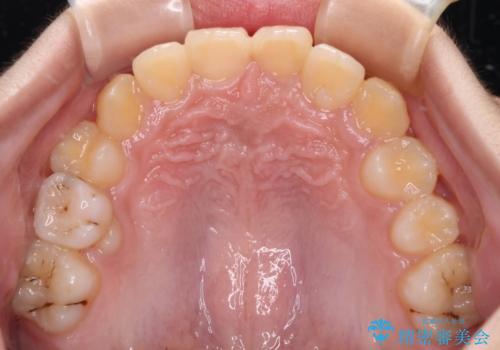

- 前歯の叢生を気にして来院された、小学校3年生女児の患者様です。

身長がやや低く、乳歯から永久歯への交換が少し遅い印象があったので、ワイヤー装置による1期矯正治療ではなく、乳歯も積極的に動かすことのできるインビザライン・ファーストにて治療を行うこととしました。

上顎前歯に過剰歯があったため、まずはその歯を抜歯し、傷が治癒したタイミングでインビザラインを発注することとしました。

インビザライン・ファーストは1.5年から2年程度の治療期間という制約がありますが、成人矯正(2期治療)をスムーズに行うための下準備期間として位置づけられており、2期治療を比較的安価かつ短期間で行うことができるようになります。